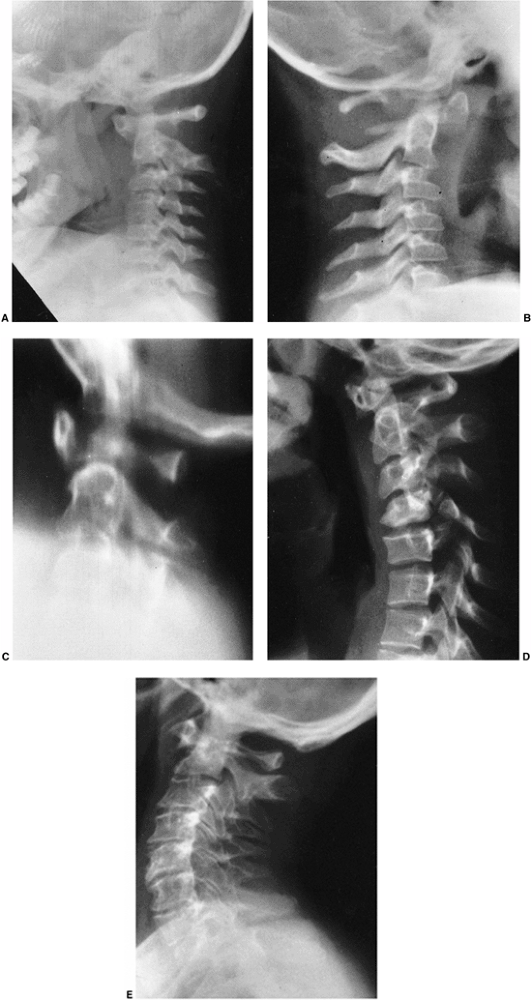

Figure 9.3 Scoliosis (A, B) and protrosia of the hips (E) in a patient with Marfan syndrome. C, D:

Deformity of the apical vertebrae is shown in a three-dimensional reconstruction of a computerized tomographic scan image. (Courtesy of Chris Reily, MD, Vancouver, British Columbia, Canada.) |

dysplastic (Fig. 9.3). The spinal deformity is

often associated with kyphosis, especially in the lumbar spine region.

Protrusio acetabula is present in about one-third of patients with

Marfan syndrome. It is not related to bone mineral density and is

usually asymptomatic (39), and thus prophylactic fusion of the triradiate cartilage is probably not warranted.